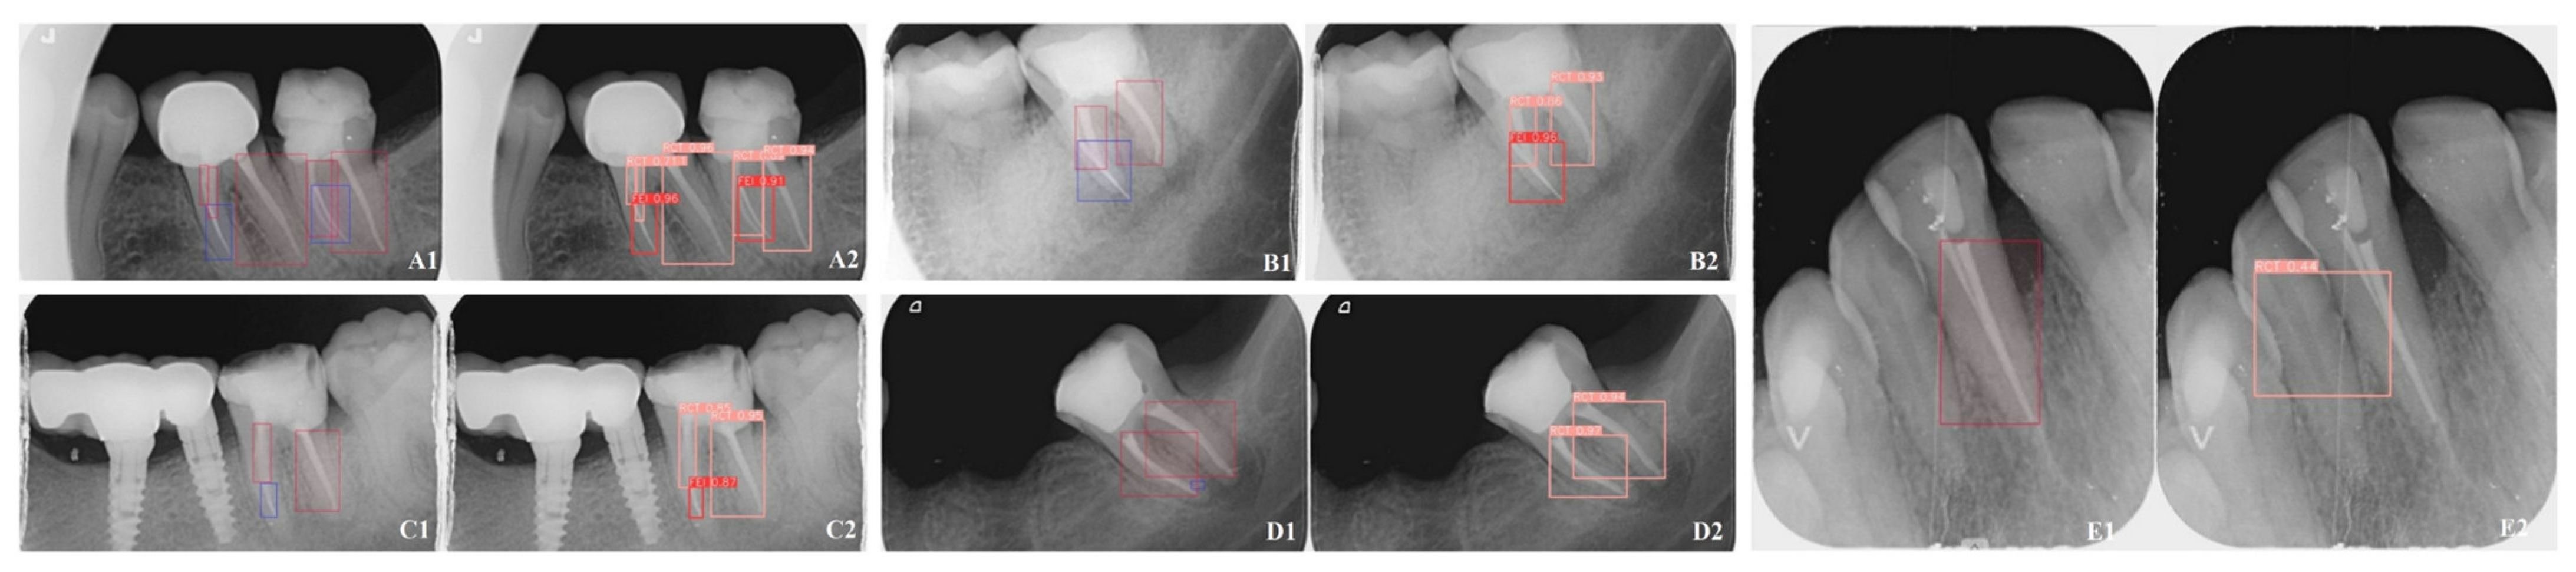

| Accuracy | IoU (Intersection Over Union) | mAP50 | Interference Time | |

|---|---|---|---|---|

| YOLO v8 | 0.973975 | 1.00 | 0.989 | 14.6 ms |

| Mask-R-CNN | 0.982075 | 0.99 | 0.950 | 88.7 ms |

| p | 0.571 | 0.146 | 0.020 |

| Endodontist A | Endodontist B | Mask-R-CNN | YOLOv8 | A-B (p) | A- Mask-R-CNN (p) | A- YOLOv8 (p) | B- Mask-R-CNN (p) | B- YOLOv8 (p) | Mask-R-CNN-YOLOv8 (p) | |

|---|---|---|---|---|---|---|---|---|---|---|

| BG F1 Score | N/A | N/A | 0.9893 | N/A | --- | --- | --- | --- | --- | --- |

| FEI F1 Score | 0.9947 | 0.9947 | 0.9890 | 1.0000 | 1.000 | 0.640 | 0.447 | 0.640 | 0.447 | 0.272 |

| RCT F1 Score | 0.9944 | 0.9944 | 1.0000 | 0.9964 | 1.000 | 0.447 | 0.832 | 0.447 | 0.832 | 0.542 |

| BG- FEI (p) | --- | --- | 0.971 | --- | ||||||

| BG- RCT (p) | --- | --- | 0.064 | --- | ||||||

| FEI- RCT (p) | 0.967 | 0.967 | 0.126 | 0.382 |